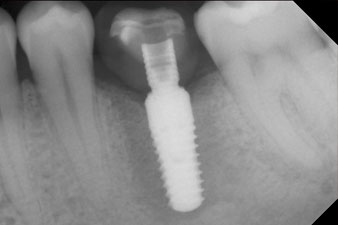

The final pictures show the screw-retained monolithic composite crown in place and the x-ray check (Fig. 9 and 10) (6).